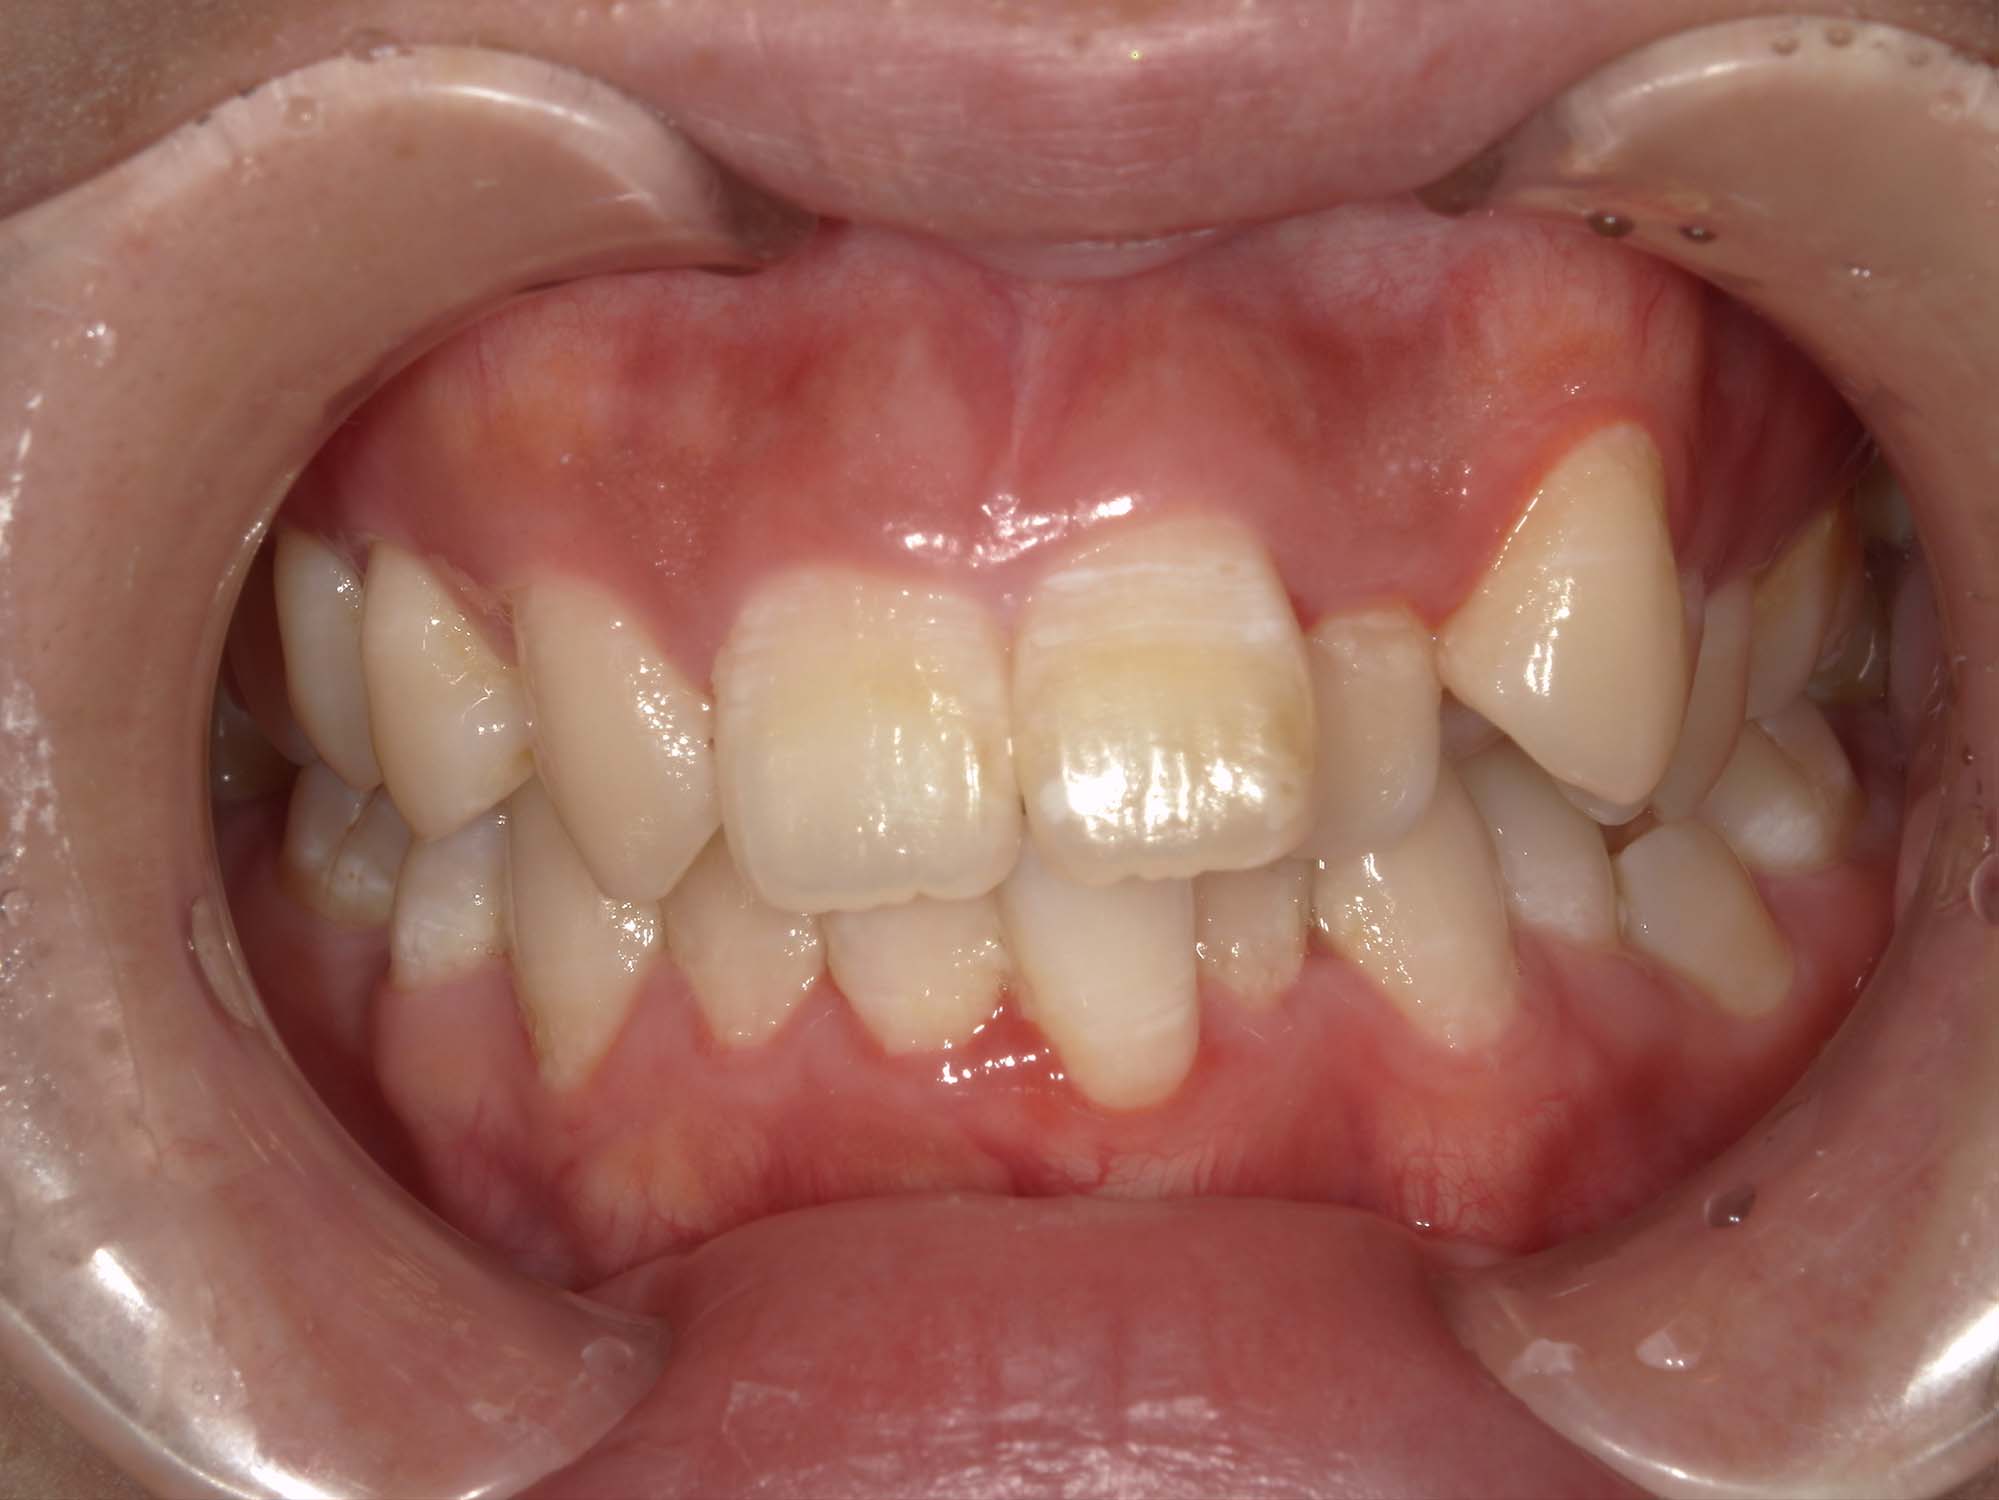

| 年齢・性別 | – |

|---|---|

| 主訴 | 叢生が気になる |

| 治療期間・回数 | 1年 |

| 費用 | 935,000円 |